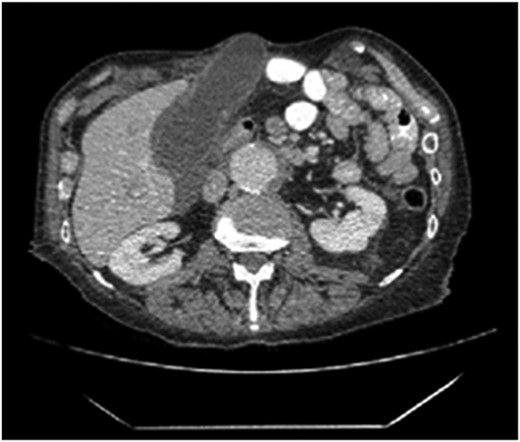

Seventy-six-year-old male with a past medical history of COPD and esophageal cancer status post gastric pull-through procedure 25 years prior, presented to the Emergency Department with a chief complaint of sudden onset epigastric pain that began 24 hours prior while at rest. The pain progressively worsened and radiated to both his right upper quadrant and back with associated chills and nausea/vomiting. He was found to be febrile (38.1C) with a leukocytosis (18.77), hyperbilirubinemia (2.8), transaminitis (418/196) and elevated alkaline phosphatase (168) and lipase (>2250). A CT abdomen/pelvis with IV contrast demonstrated a thickened gallbladder wall, pericholecystic fluid and associated edema of the pancreas consistent with acute cholecystitis and pancreatitis. While the CT showed postoperative changes given his history of esophagectomy with gastric conduit, multiple unique anatomic abnormalities were also noted, including the presence of the gallbladder through a ventral hernia to where it was flush with the skin/subcutaneous tissue of the anterior abdomen (Figs 1 and 2). By hospital day 2, the patient’s lab values were downtrending, consistent with a transient common bile duct stone. Follow-up MRCP confirmed the diagnosis of acute calculous cholecystitis with obstruction of the cystic duct and patency of the common bile and pancreatic ducts. The decision was made to take the patient to the operating room for cholecystectomy with cholangiography. In the operating room, a right subcostal incision was made using electrocautery with a hernia sac encountered directly deep to the subcutaneous tissue. The peritoneum of the hernia was opened and the tip of the gallbladder was immediately encountered. On gross examination, necrosis was noted with evidence of microperforation into the hepatic plate, though no gross contamination was present. The gallbladder was dissected off the hepatic plate, the cystic artery was identified and ligated and stones palpable within the cystic duct were milked retrograde prior to ligation of the cystic duct. The gallbladder was removed and sent for definitive pathologic review. The hernia sac and skin were reapproximated in a multi-layered closure but the fascial edges were not amenable to primary closure secondary to both chronicity and size of the incisional hernia. The patient tolerated the procedure well and was able to discharge home on hospital day 5 (Post-operative day 3). Final pathology was consistent with acute calculous gangrenous cholecystitis. The patient was seen for follow-up 1 month post-operatively and was doing well with no complaints or return of symptoms.

The axial section of the abdomen/pelvis CT scan illustrating our patient’s incisional hernia containing his gallbladder.